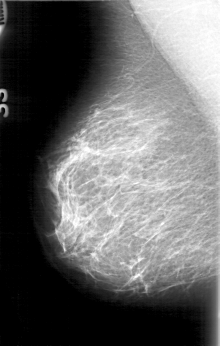

D_4075_1.RIGHT_CC

RIGHT_CC LINES 5266 PIXELS_PER_LINE 3076 BITS_PER_PIXEL 12 RESOLUTION 43.5 NON_OVERLAY

RIGHT_MLO LINES 5176 PIXELS_PER_LINE 3286 BITS_PER_PIXEL 12 RESOLUTION 43.5 NON_OVERLAY